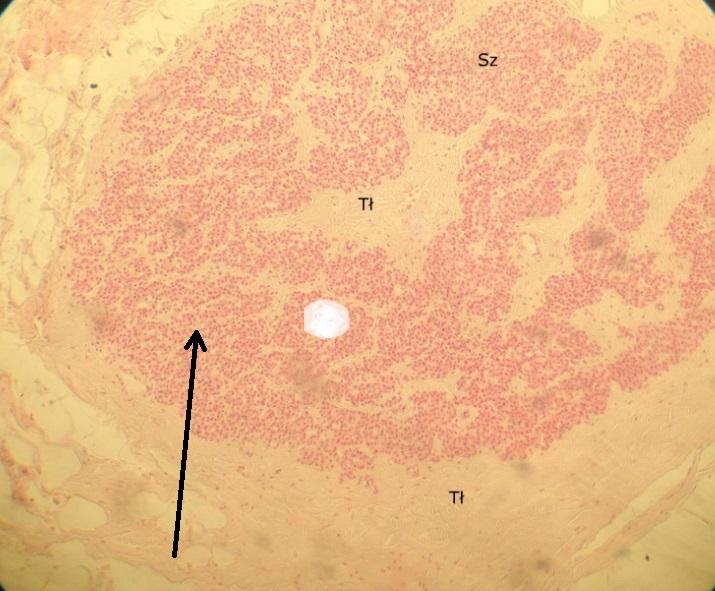

tkanka tłuszczowa żółta (tarczyca)